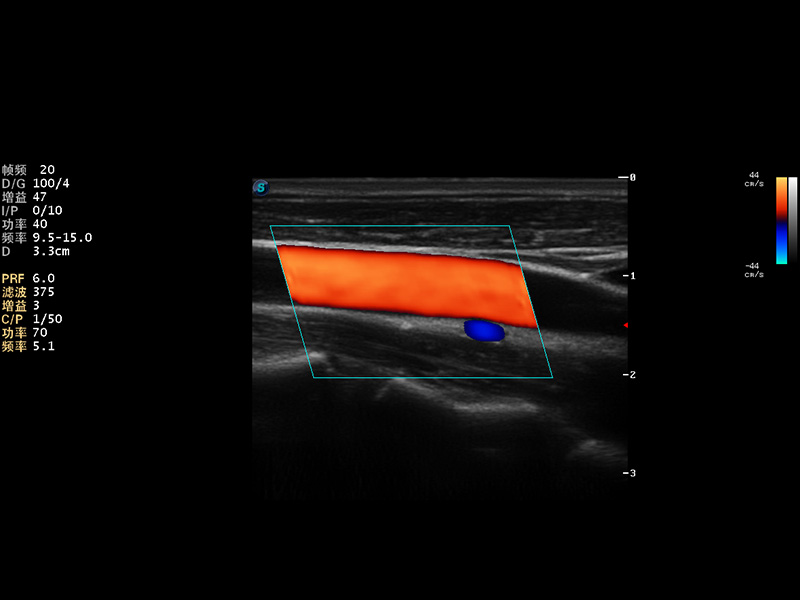

S9便携式彩色多普勒超声诊断仪是诸侯快讯官网研发的高端便携彩超设备,外观设计新颖、产品性能卓越。S9在便携超声领域采用了突破传统的触摸屏交互设计,并以先进的软件硬件技术和设计理念,为您带来清晰的图像质量、稳定的工作性能和便捷的操作体验。

AutoC智能血流追踪